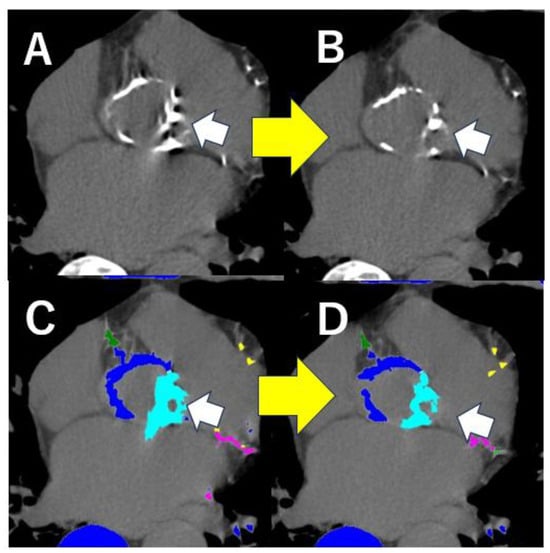

- Saito, Y.; Takaoka, H.; Funabashi, N.; Ozawa, K.; Tamura, Y.; Saito, M.; Matsumiya, G.; Kobayashi, Y. A case of very severe aortic stenosis due to unicuspid aortic valve mimicking bicuspid aortic valve with calcification on cardiac computed tomography. Int. J. Cardiol. 2016, 215, 516–518. [Google Scholar] [CrossRef]